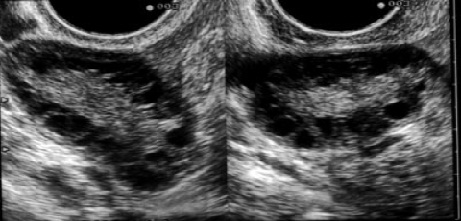

Õppematerjal "Hüperandrogeneemia" on koostatud sünnitusabi ja günekoloogia eriala spetsialistele, doktorantidele ja residentidele. Õppematerjal koosneb ühe haigusjuhu analüüsist ja teoreetilisest osast, kus antakse ülevaade steroidhormoonide ainevahetusest, rõhuasetusega androgeenidele, hüperandrogeneemia patogeneesist, kliinilistest sümptoomidest, diagnoosimisest ja ravist.